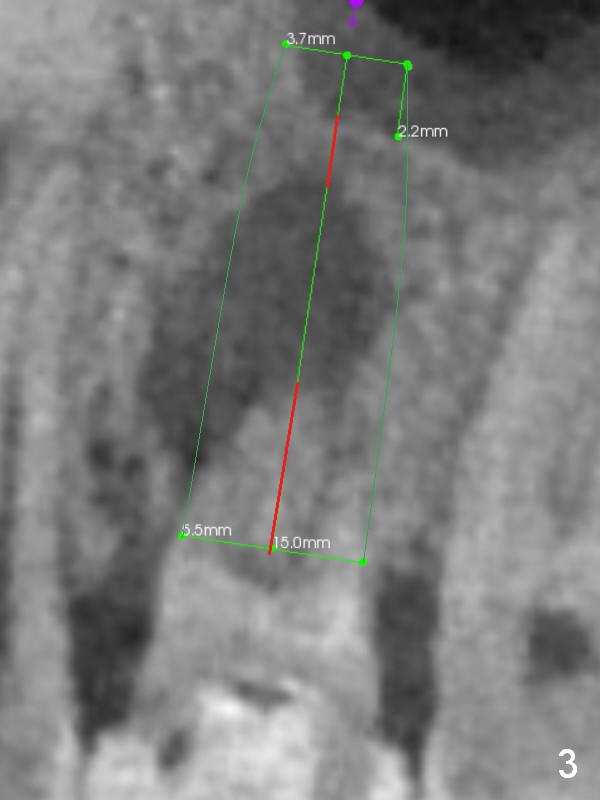

A 34-year-old man has persistent large periradicular radiolucency (Fig.1) after root canal therapy with a fistula (Fig.2). It appears that immediately after extraction (no Antibiotic) a long implant (15 or 16 mm, green outline) should be placed to bypass the bony defect with 2-point fixation (septum and sinus floor; Fig.3 (CBCT sagittal section), 4 (coronal section) red line). A shorter implant, which is placed at the septum (4-5 mm tall), is not expected to be stable. The diameter of the implant is to be determined after sequential osteotomy. The minimal will be 4 mm (Fig.5 axial section) as long as the implant or osteotomy does not perforate the palatal (P) or buccal (B) socket substantially. The bone density at the septum and the sinus floor is 1100 and 200-400 units, respectively. Drills and osteotomes (Tatum or Magic Expanders) will be used for osteotomy in these 2 segments, respectively.